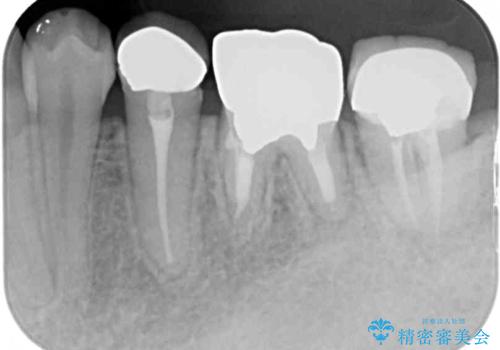

- 他院で抜歯矯正を終えた後、銀色の目立つ奥歯を白くしたいとのことで来院された患者様です。

既にセラミッククラウンが装着されている歯もありますが、不自然な色合いや黒い縁も気になるので、一斉に補綴治療をして統一感を持たせることとしました。

矯正治療を終えたばかりなので、仮歯やセラミッククラウンに置き換えている間に保定がうまくいかなくなる可能性があるため、下顎前歯の舌側を事前にワイヤーで保定しておくこととしました。